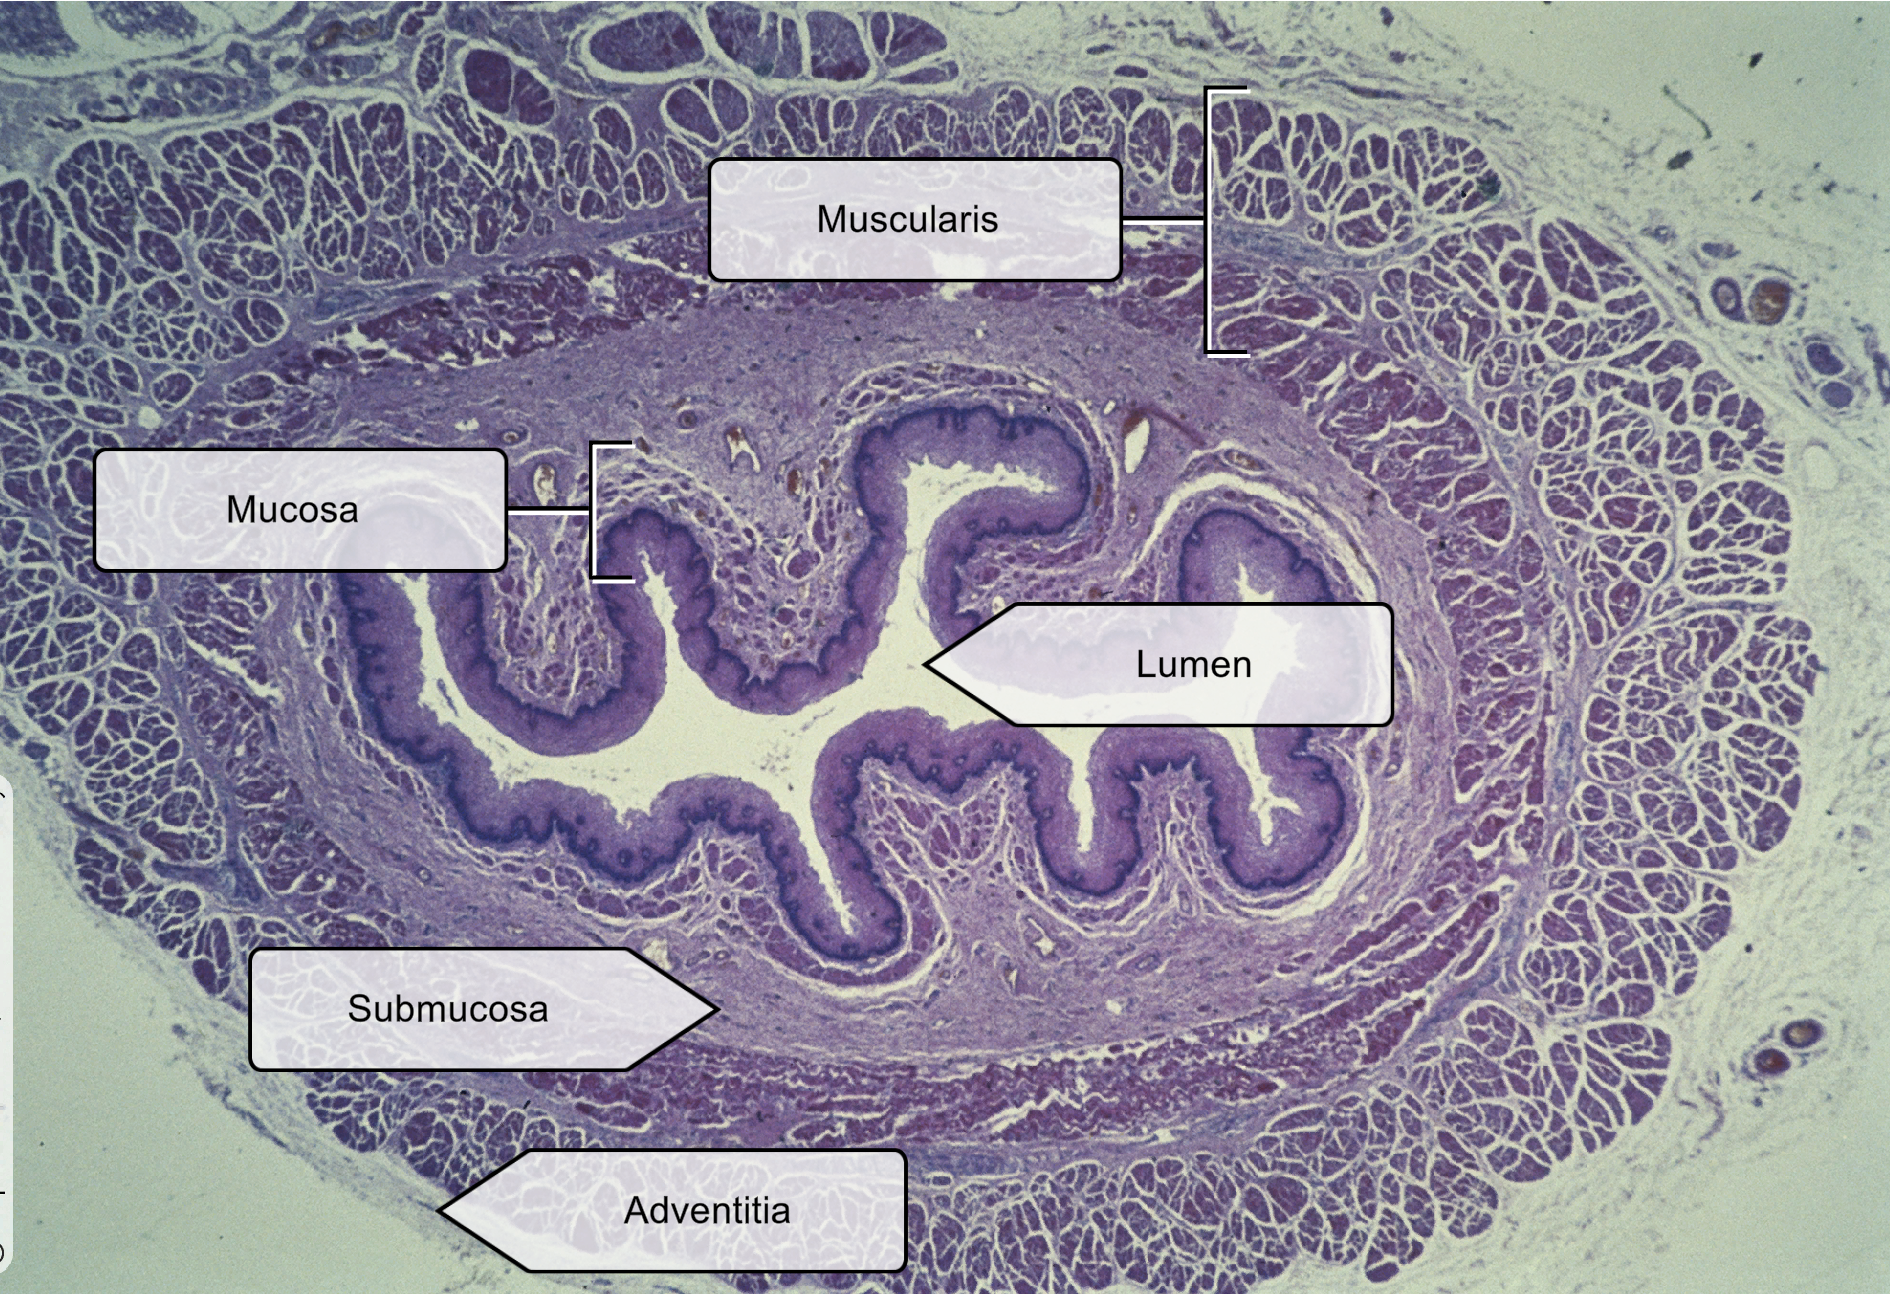

list the four layers of Esophagus cross section

Mucosa layer- stratified squamous epithelium, non-keratinized